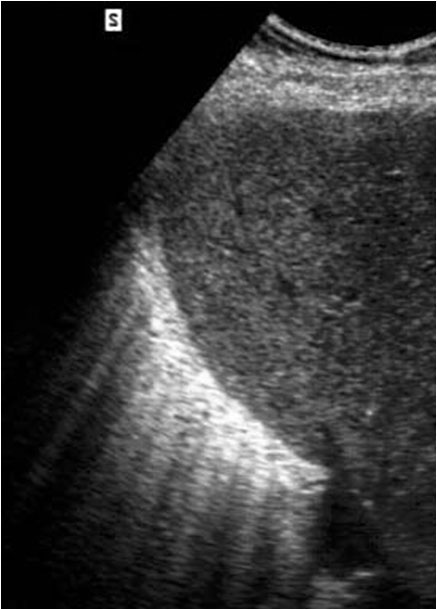

Este signo nos permite diferenciar entre derrame pleural y ascitis en un estudio de TC. Cuando existe una interfase nítida entre líquido y el hígado o el bazo, se trata de ascitis; cuando la interfase no es nítida, se trata de derrame pleural (flecha). El derrame pleural ocupa una posición más posterior y medial, mientras que la ascitis se localiza anterior y lateral al hígado y al bazo.

Esta segunda imagen corresponde a ascitis. Observa como la interfase entre el bazo y el líquido (flecha) es más nítida que en la imagen anterior. También lo es la interfase entre el hígado y el líquido.

SIGNO DEL ÁREA DESNUDA

Cuando en la TC vemos líquido en situación dorsal al hígado (flecha), éste se encuentra en la cavidad pleural, ya que el líquido intraperitoneal no puede acumularse en esta zona debido a que el peritoneo se repliega sobre la cúpula hepática sin llegar a cubrir la parte posterior del hígado, es decir, que no hay cavidad peritoneal por detrás del hígado y, por tanto, la ascitis no puede ocupar este espacio.

En esta imagen también está presente, lógicamente, el Signo de la interfase.

En la imagen correspondiente a ascitis que presentamos en el signo anterior, observa cómo se respeta la zona posteromedial del hígado.